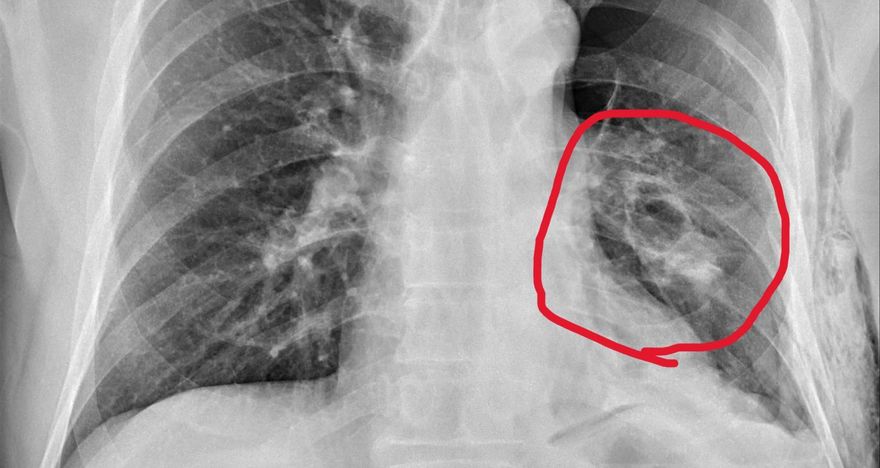

他車禍後兩天才就醫!肋骨斷4根、脾臟破裂差點丟命

肋骨骨折

氣胸

脾臟破裂